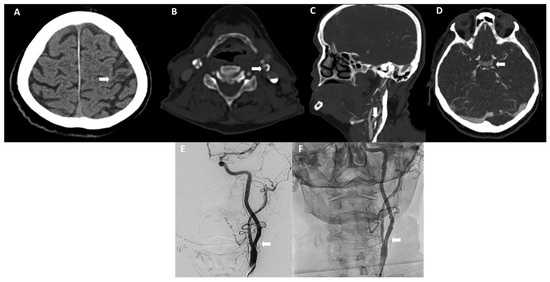

Post-Carotid Artery Stenting Hyperperfusion Syndrome in a

• Patient Selection Criteria and Procedural Standardization

• Post-Carotid Artery Stenting Hyperperfusion Syndrome in a